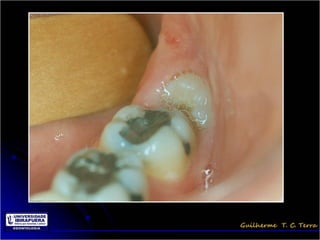

Pericoronarite

• Infecção dos tecidos moles (Opérculo)

que recobrem a coroa de um dente

incluso

• A dificuldade de higienização sob o

opérculo

Tratamento da Pericoronarite

• Limpeza mecânica do opérculo através de

irrigação com soro ou água oxigenada 10 vol

• Higienização dolocal pelo paciente e irrigações

com água oxigenada 10 vol

• Antibioticoterapia

• Exodontia